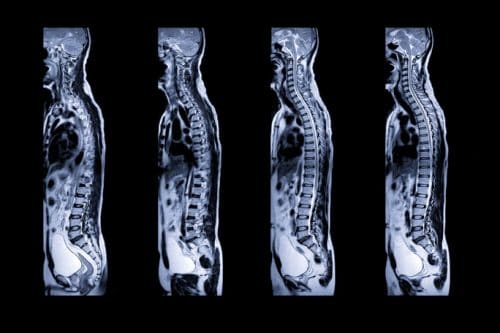

Learn the Basics of Spinal Cord Injuries and Personal Injury Lawsuits in California

There are millions of nerve fibers within the human spine. Each of these fibers transmits info between the brain and body. Any trauma to any part of the spinal cord can cause an injury, ranging from minor to life-ending. Read on to learn the basics of spinal cord injuries and then contact The Law Offices of Larry H. Parker at 800-333-0000 if you require the help of a personal injury attorney.